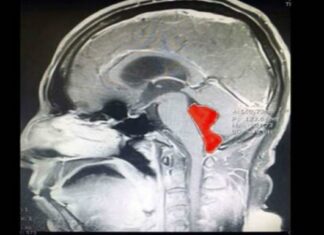

Άνδρας ζούσε με φρικτούς πονοκεφάλους και έκανε εμετούς! Μόλις πήγε στους γιατρούς έμειναν με...

Άνδρας ζούσε με φρικτούς πονοκεφάλους που του προκαλούσαν εμετούς! Έτσι λοιπόν αποφάσισε να πάει στους γιατρούς, οι οποίοι έμειναν με το στόμα ανοικτό με αυτό που ανακάλυψαν ότι ζούσε μέσα του! Από τη...